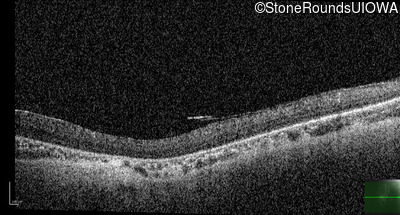

Optical Coherence Tomography - Left - 10/350 sc

Exemplar / OCT Stack

OCT Stack